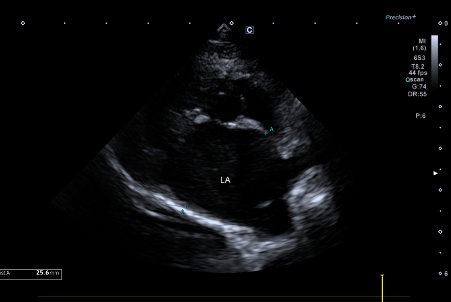

RPS long axis view에서 좌심방 너비 25.6mm로 측정되어 좌심방이 심하게 확장된 상태가 확인되었습니다.

환자의 심장초음파 사진(RPS long axis view 상 좌심방 너비 25.6mm 심한 확장)/출처: 24시 동탄리더스동물의료원